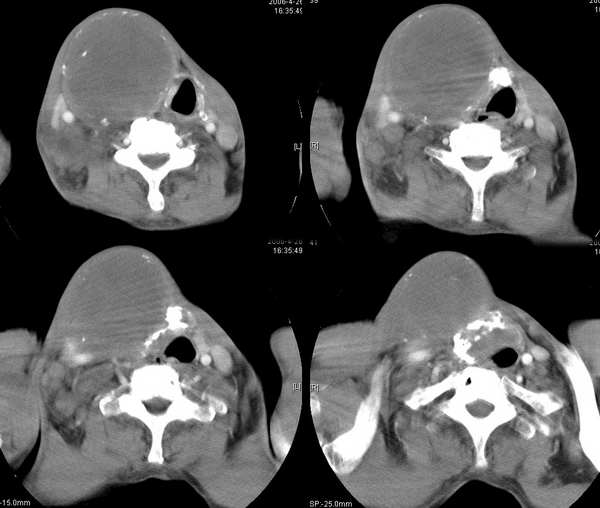

男,74岁,甲状腺肿30余年。现右颈部出现新肿块,疼痛,感乏力。

右颈部巨大软组织肿块影,范围较广,上至下颌角,下至颈静脉切迹。其最大层面位于右侧甲状腺区。肿块密度不均,其中有坏死液化区和班片状钙影,增强扫描见肿块实质区有强化。邻近结构挤压移位,部分结构侵蚀破坏,右侧多个颈深淋巴结肿大。两肺弥漫分布小结节影,以胸膜下为主,其大小不等,边缘光整。右侧胸壁亦见软组织结节影,纵隔多个淋巴结肿大及两侧锁骨上淋巴结肿大。

意见:右侧甲状腺癌并两肺、胸壁、纵隔淋巴结、颈深淋巴结、锁骨上淋巴结等广泛转移。